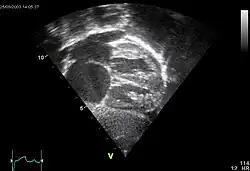

In transthoracic echocardiography, an atrial septal defect may be seen on color flow imaging as a jet of blood from the left atrium to the right atrium.

If agitated saline is injected into a peripheral vein during echocardiography, small air bubbles can be seen on echocardiographic imaging. Bubbles traveling across an ASD may be seen either at rest or during a cough. (Bubbles only flow from right atrium to left atrium if the right atrial pressure is greater than left atrial). Because better visualization of the atria is achieved with transesophageal echocardiography, this test may be performed in individuals with a suspected ASD which is not visualized on transthoracic imaging. Newer techniques to visualize these defects involve intracardiac imaging with special catheters typically placed in the venous system and advanced to the level of the heart. This type of imaging is becoming more common and involves only mild sedation for the patient typically.

If the individual has adequate echocardiographic windows, use of the echocardiogram to measure the cardiac output of the left ventricle and the right ventricle independently is possible. In this way, the shunt fraction can be estimated using echocardiography.

ASD with pulmonary embolism resulting in a right-to-left shunting of blood[39]

-